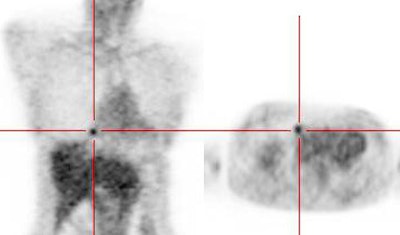

Atypical carcinoid tumor: The patient presented for evaluation of a right lung nodule. The nodule was positive on PET imaging and was surgically resected. The nodule proved to be an atypical carcinoid tumor. Most carcinoids are not positive on PET imaging, however, atypical carcinoids are more aggressive lesions and this may explain the FDG accumulation. Unfortunately, the patient had ipsilateral hilar lymph node metastatses which were not seen on CT or on PET imaging. |

|